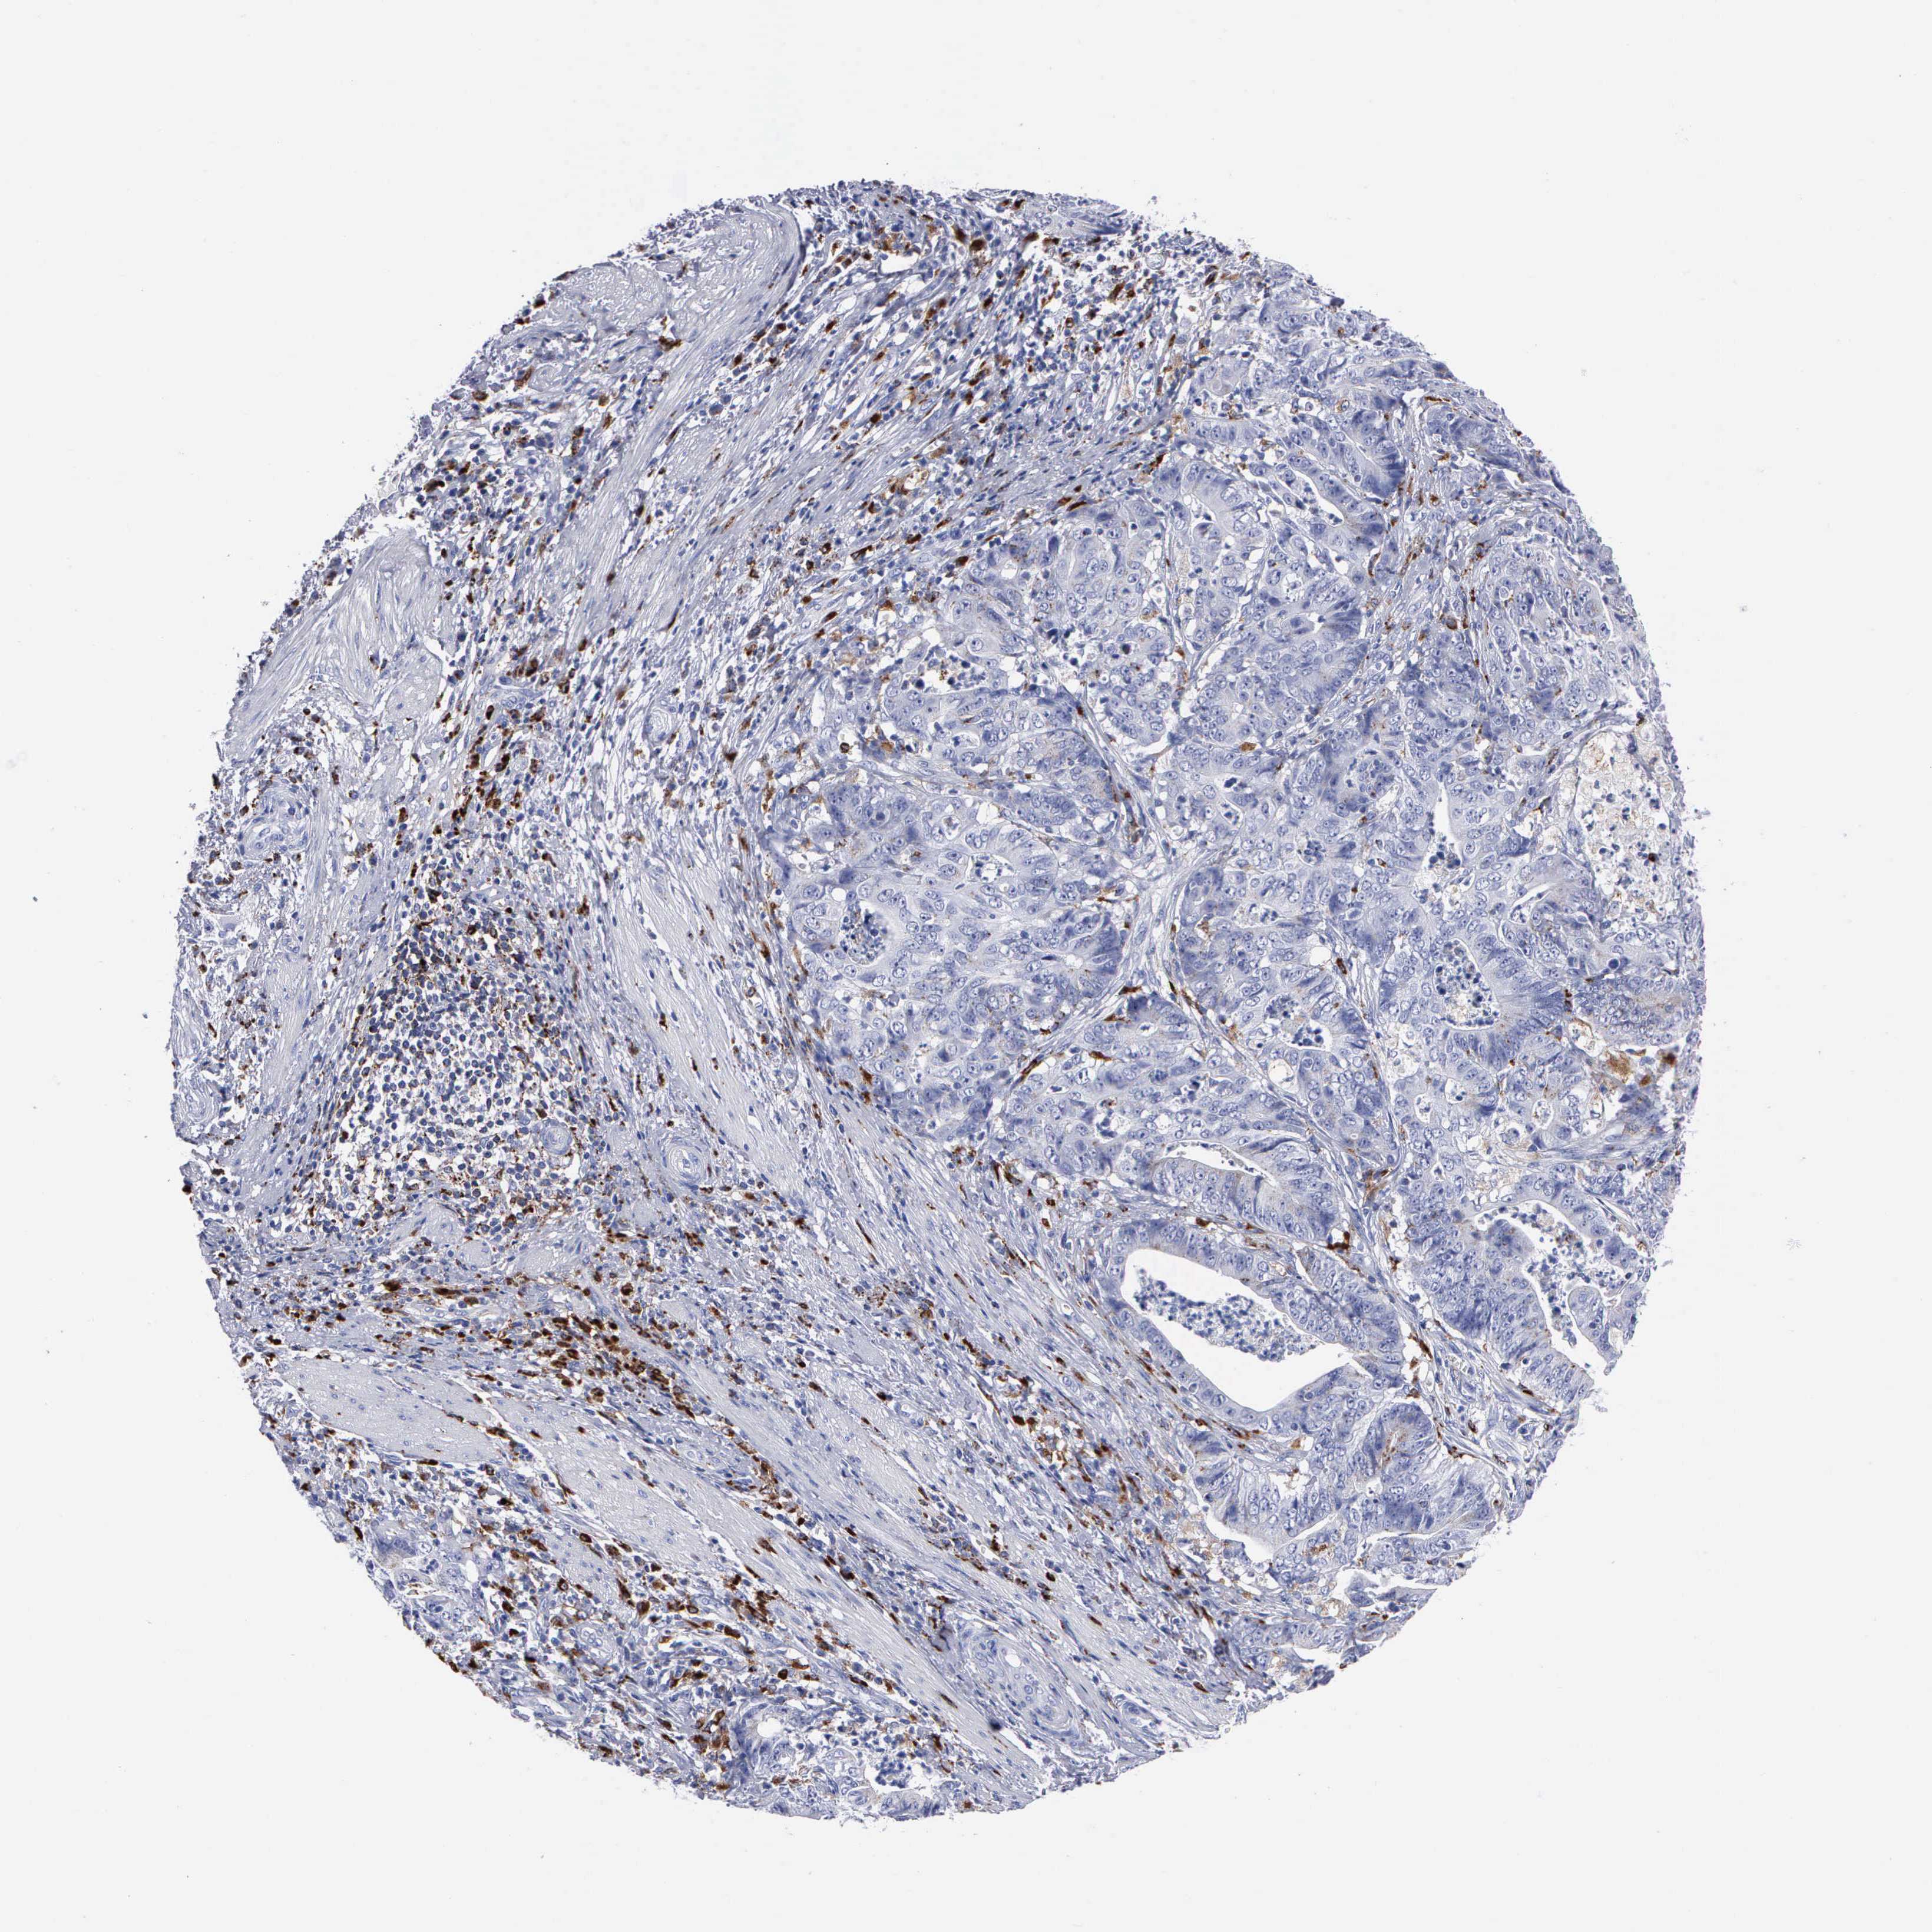

STOMACH CANCER - Protein expressioni

A mouse-over function shows sample information and annotation data. Click on an image to view it in a full screen mode. Samples can be filtered based on level of antibody staining by selecting one or several of the following categories: high, medium, low and not detected. The assay and annotation is described here.

Note that samples used for immunohistochemistry by the Human Protein Atlas do not correspond to samples in the TCGA dataset.

Antibody stainingi

Antibody staining in the annotated cell types in the current human tissue is reported as not detected, low, medium, or high, based on conventional immunohistochemistry profiling in selected tissues. This score is based on the combination of the staining intensity and fraction of stained cells.

Each image is clickable and will lead to virtual microscopy that enables deeper exploration of all samples and also displays staining intensity scores, fraction scores and subcellular localization as well as patient and tissue information for each sample.

Antibody HPA003524

Antibody CAB000458

Staining

High

Medium

Low

Not detected

Intensity

Strong

Moderate

Weak

Negative

Quantity

>75%

75%-25%

<25%

None

Location

Nuclear

Cytoplasmic/membranous

Cytoplasmic/membranous,nuclear

Adenocarcinoma, NOS